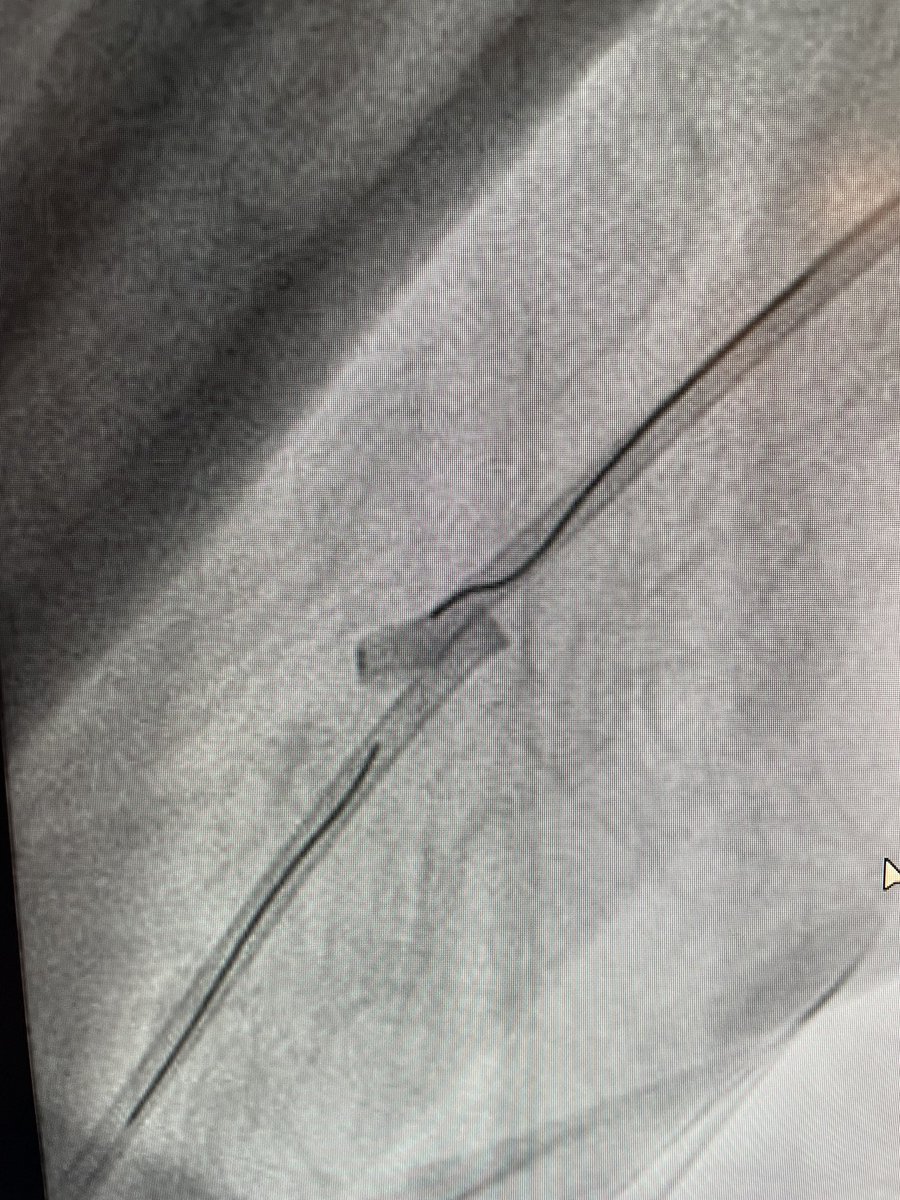

@perc_surgeon Same thing happened to me 2 days ago! JR4 guide kinked at forearm. Fem access with MPA and Tulip snare to dekink. @AmmarNasirMD